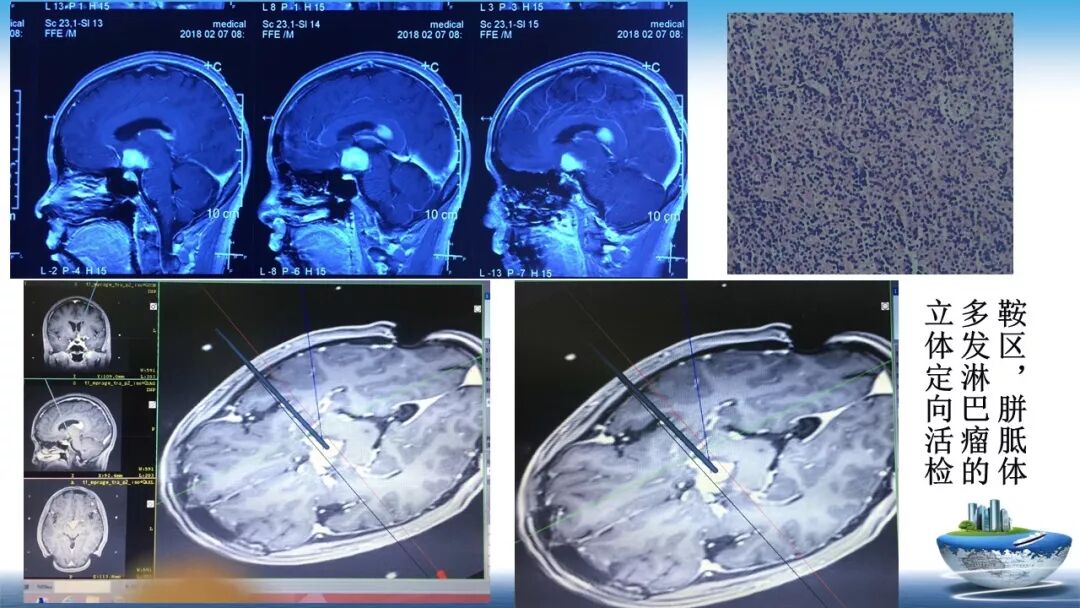

立体定向活检在脑干中线病变精准诊断中的作用

今天为大家带来的是中国人民解放军总医院第六医学中心(原中国人民解放军海军总医院)王亚明、于新、张剑宁带来的精彩课题分享:立体定向活检在脑干中线病变精准诊断中的作用,欢迎观看、阅读!